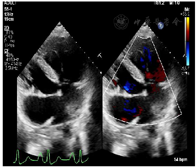

患者入院查体:体温36.4℃,脉搏98次/分,呼吸21次/分,血压147/91 mmHg;SPO2 60%;发育正常,营养中等,无病容,表情自如,神志清楚,自主体位,查体合作。口唇明显青紫,面部青紫,双肺呼吸音清,未闻及明显干湿啰音,心音可,律齐,P2<A2,胸骨左缘2、3、4肋间闻及2-3/6级粗糙的收缩期杂音。腹部平坦,腹壁软,全腹无压痛,无反跳痛、肌紧张反跳痛、肌紧张,肝肋下未触及,胆囊未触及,脾不大,无移动性浊音,双侧肾区无叩痛,肠鸣音正常。双下肢无水肿。四肢末梢青紫,伴杵状指(图1)。

入院后,完善各项术前检查,包括心脏超声(图2),心脏及大血管CT(图3),调整患者营养状况,进行呼吸功能训练并多次进行多学科团队讨论。最后明确术前诊断:先天性心脏病:矫正型大动脉转位,室间隔缺损,肺动脉及其瓣下狭窄,二尖瓣中量返流,体肺侧支循环,间断加速性室性自主心律,室性早搏,房性早搏。